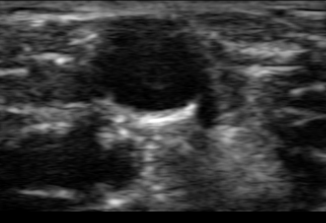

USS vein.PNG

Online Learning course for USS IV access

Dr Jame Rippey (Perth Australia) has set up an online free course and material for learning IV access with ultrasound. This is aimed to be part of a course and when we run it will be part of the pre-reading.

For when we are not running a course it is still useful learning. Please though get someone who is signed off to supervise your first few and remember ultrasound is slower and MORE problems in an easy cannulation than without,

(such as the image to the left)